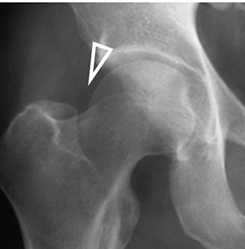

Se produce por el sobrecubrimiento de la cabeza femoral, por la cavidad acetabular (26). (Fig 93).

Fig 93. Pinzamiento tipo pincer.

Rx AP. Ocasionado por sobrecubrimiento acetabular.